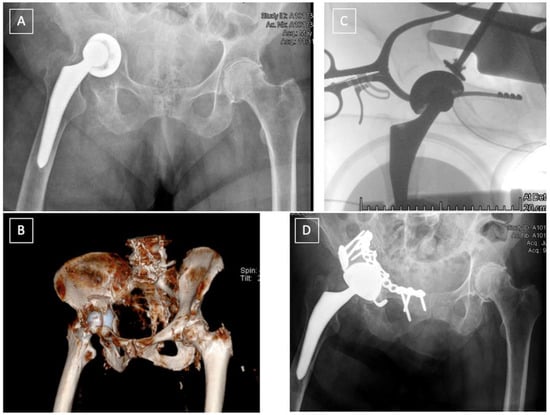

3. Diagnosis

4. Treatment

4.2. Post-Operative Fractures